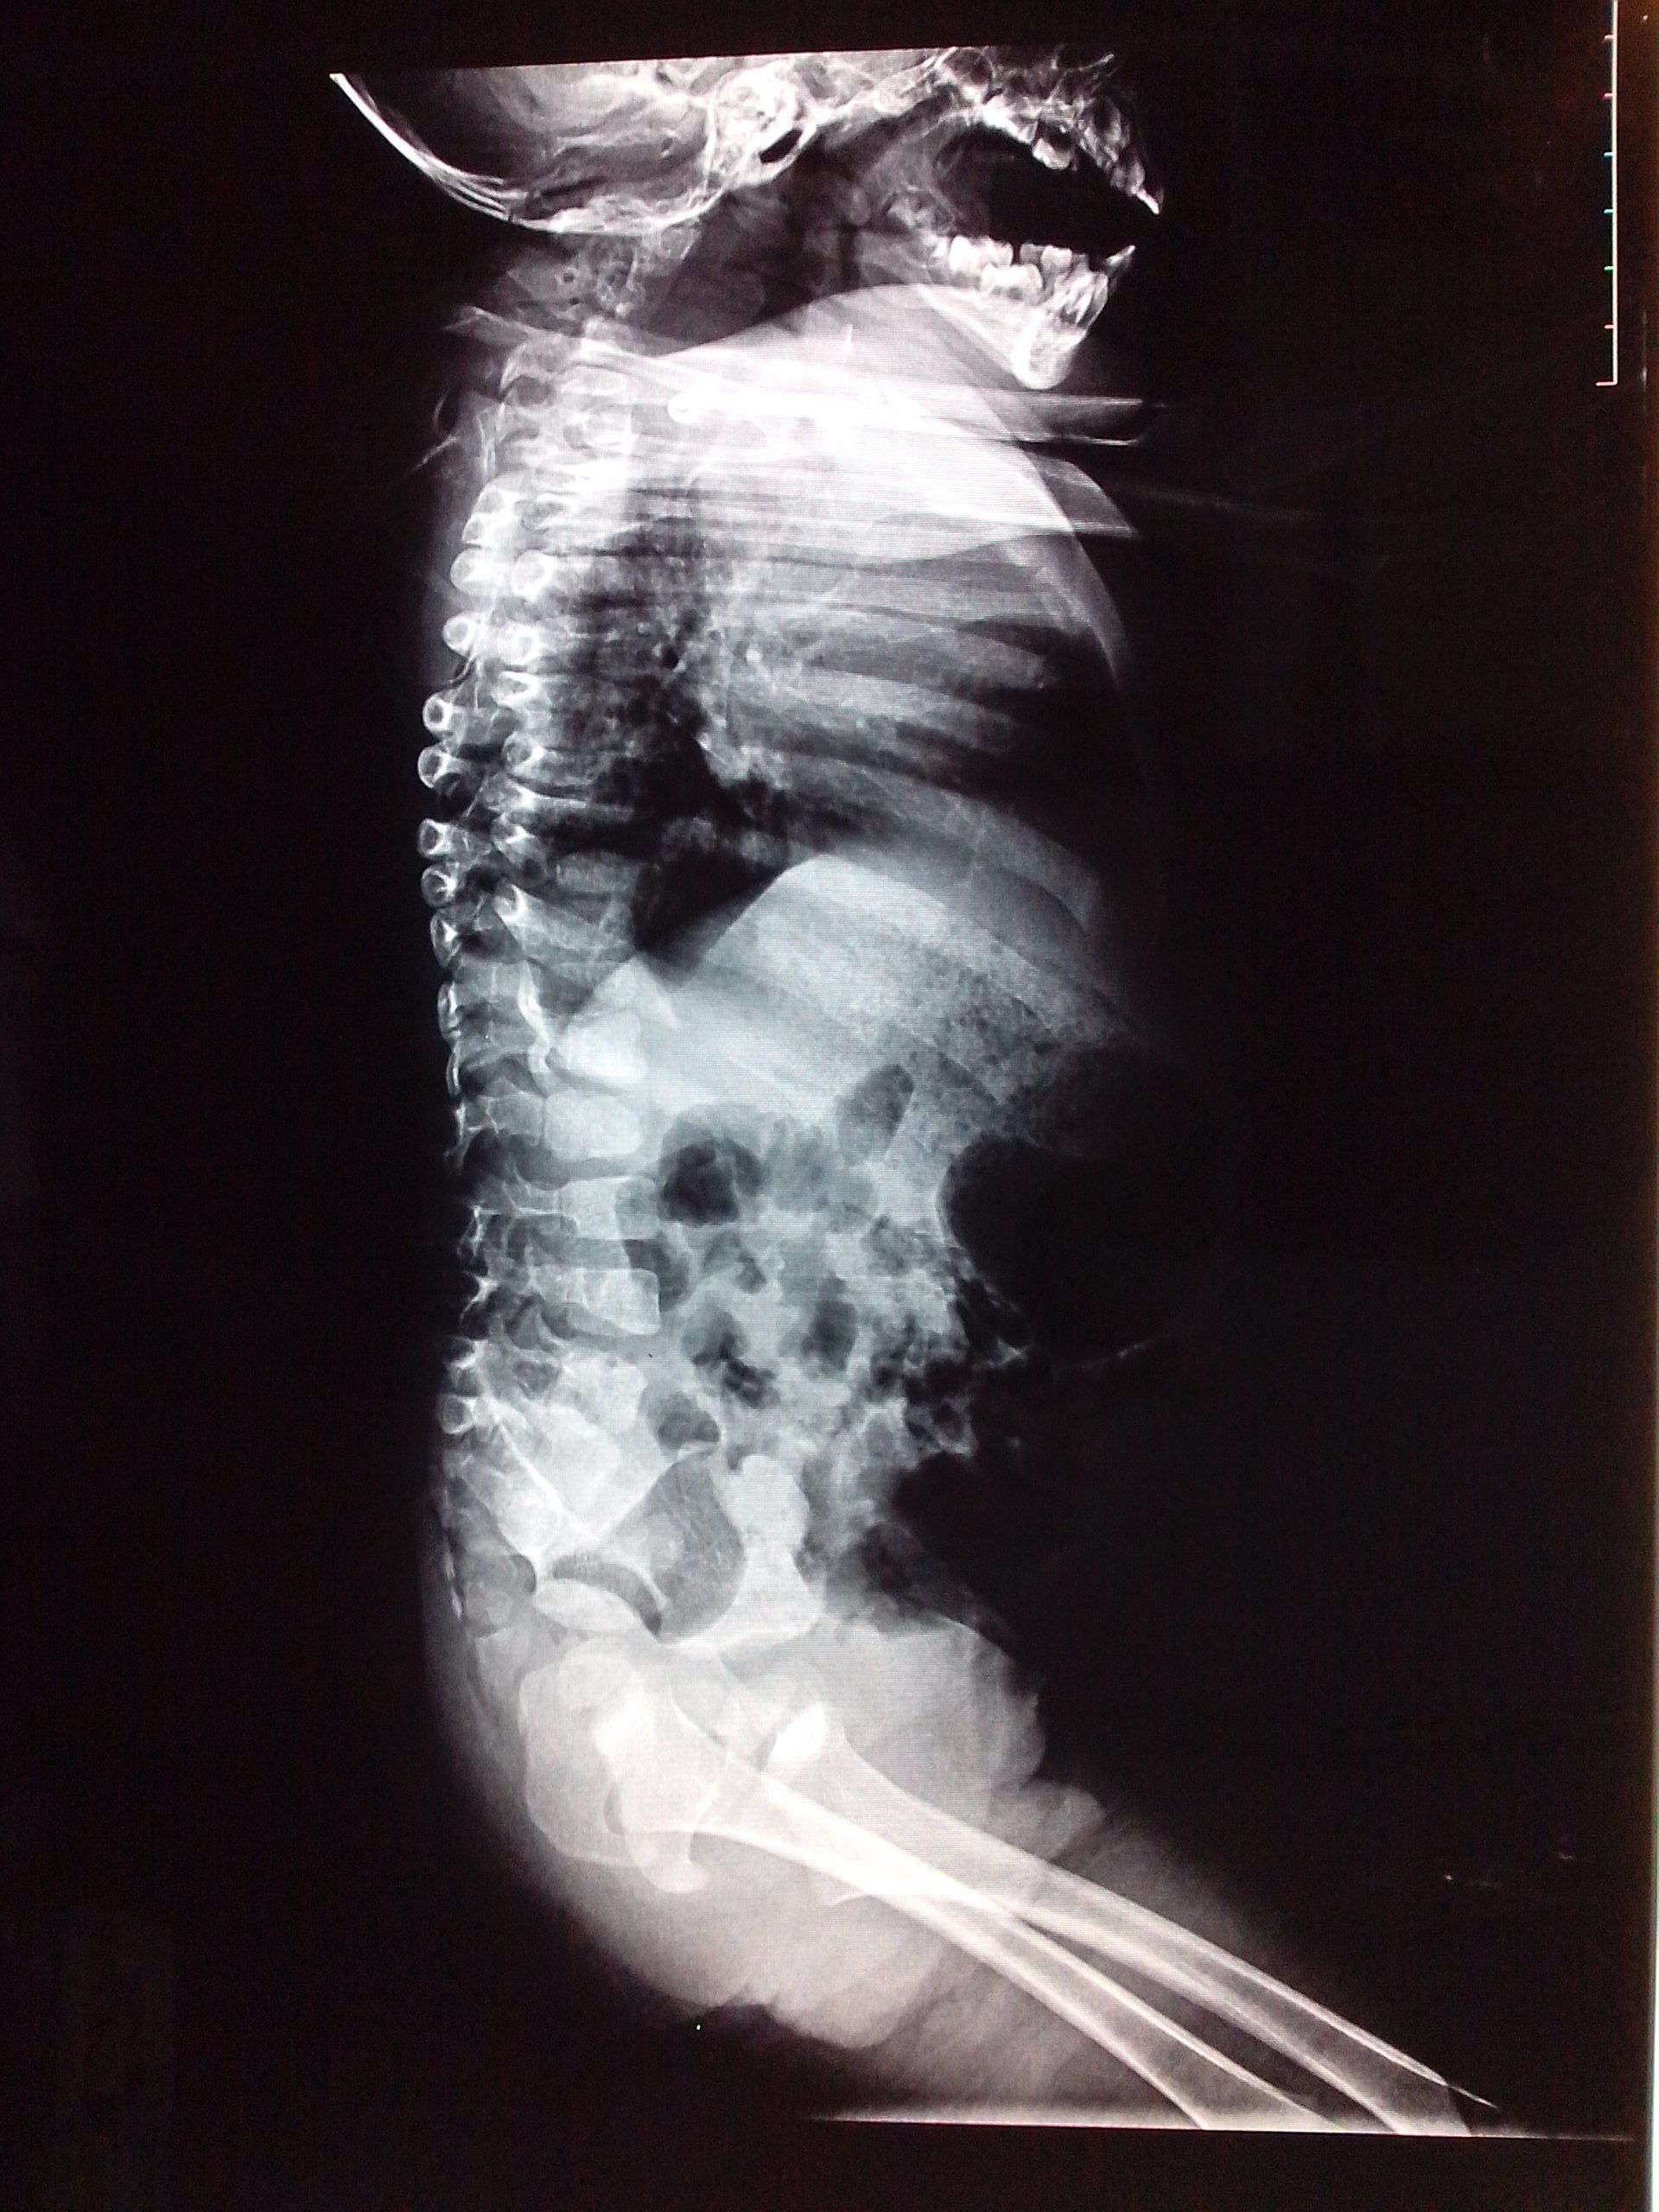

17个月幼儿个小,胸高,颈短,疑先天性疾病,如何治疗?

患者信息:男 1岁 吉林 长春 病情描述(发病时间、主要症状等):17个月幼儿个小(现在身高72cm),胸高(而且右侧明显比左侧高),颈短(且爱向右侧回头,向左侧回头费劲),之前以为是缺钙导致,后来在医院排片检查说是先天性脊柱发育不良,请问该如何治疗?何时治疗合适?(补充一下:孩子现在会走路,能说简单语言,智力正常,活泼,但是不知怎么的,自从吃了补钙药以后不怎么爱吃饭。)想得到怎样的帮助:我上传了影象,麻烦各位大夫帮看一下影象,想知道这样的病能不能治,何时治疗合适?谢谢!曾经治疗情况及是否有过敏、遗传病史:小孩之前在县医院检查说是缺钙,开了些补钙排铅和预防佝偻病的药,一直在补钙可是不怎么吸收,现在在吃迪巧儿童钙片。家人无类似病例。